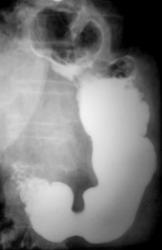

Пациент направлен на рентгенологическое исследование ЖКТР врачом терапевтом с диагнозом - "Хронический гастрит". В процессе проведения рентгенологического исследования выявлена грыжа пищеводного отверстия диафрагмы. Ваше мнение коллеги?

Картина фиксированной осевой (аксиальной) грыжи пищеводного отверстия диафрагмы, вероятно врожденный короткий пищевод (на снимке №11 виден его небольшой изгиб, но для полноценного пищевода этого недостаточно). Нарушение функции замыкающего механизма кардии. Насчет желудочно - пищеводного рефлюкса без скопии по одним снимкам неясно, во всяком случае явной перестройки складок нижних отделов пищевода нет.

Безусловно всей необходимой инфрмацией может располагать только врач проводивший конкретное исследование. Однако на всех представленных рентгенограммах нет снимка, где бы кардиальный отдел желудка был на своем законном месте - ниже купола диафрагмы, а это признак фиксированности грыжы. Хочу подчеркнуть, что неправомерно употребляемый часто нами, рентгенологами, термин "скользящая грыжа" есть не что иное - как синоним термина " аксиальная" (в отличие от параэзофагеальной), а вовсе не отражение состояния фиксированности (невправимости) или нет.